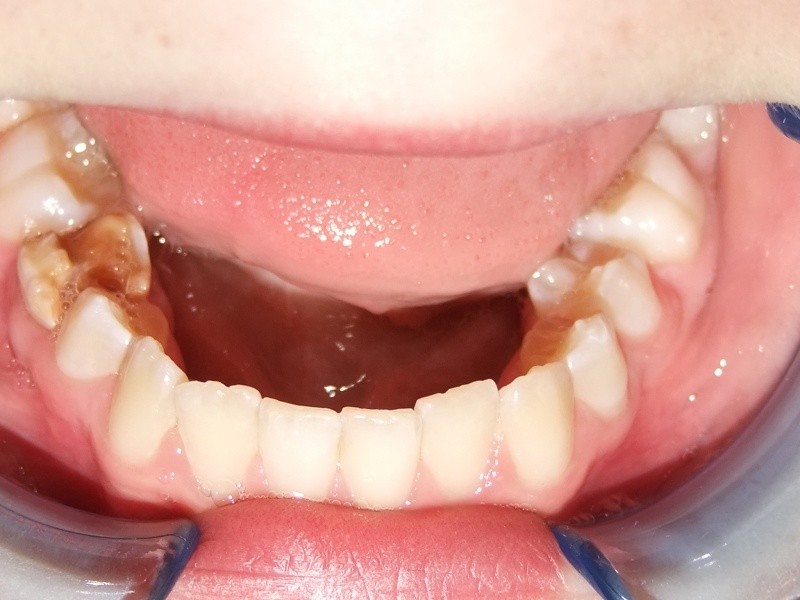

Na behandeling

Maand 7-26: Brackets en banden in bovenkaak en onderkaak

Expander in de bovenkaak

Retentie fase: Invisable Retainer en C-C- Bar

Leeftijd bij retentie fase: 13 jaar